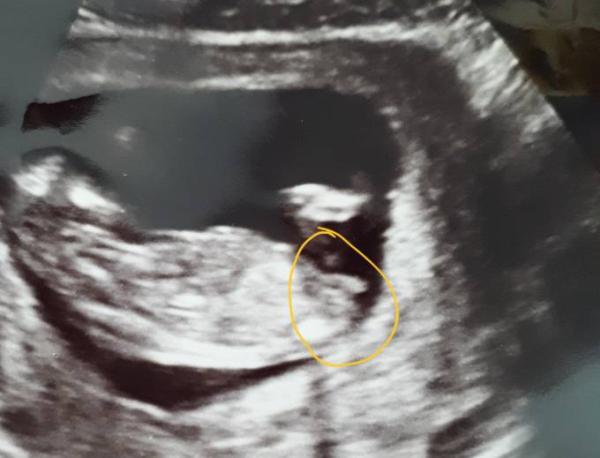

Junge oder Mädchen? 13+3

Hey ihr Lieben:) was meint ihr? Junge oder Mädchen? Liebe Grüße

Hi . Ich tippe eindeutig auf ein Mädchen. Der Nub verläuft paralell zur Wirbelsäule. LG